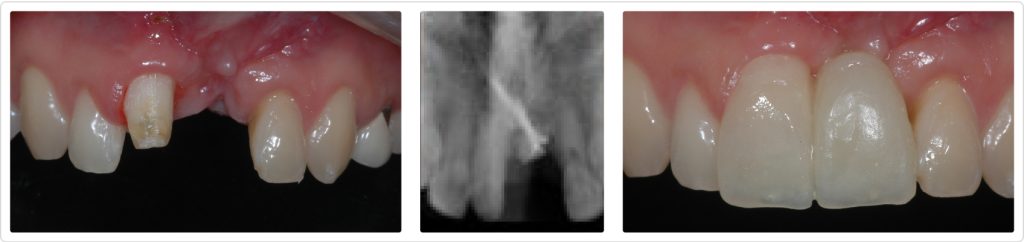

First, we surgically removed the faulty implant and placed a bone graft to compensate for the residual defect. Tooth #8 had a ceramic crown that would need to be replaced, so it was straightforward to provide a cantilever provisional restoration during the healing phase (Figs. 6–8).

The first restoration option presented was a tooth-supported cantilever fixed partial denture, but the patient wanted to know if something could be done to further enhance esthetics and functional aspects.

- Esthetically, he was aware of the lack of interproximal papilla between the central incisors and was not pleased with the overly long centrals.